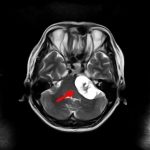

断層撮影

摘出 前

海綿状血管腫

No.’16_90 手術前1

No.’16_90 摘出 前

No.’16_90 摘出 後